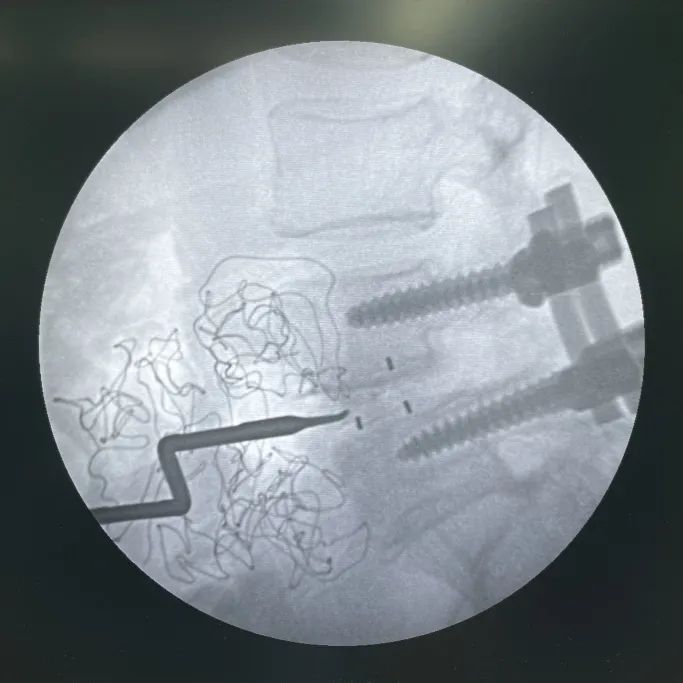

取出前次不融合的cage,并處理椎間隙

L4/L5依次試用試模,確認(rèn)Uni-L自穩(wěn)定型腰椎融合器選用大小

Uni-L自穩(wěn)定型腰椎融合器內(nèi)植骨

L4/L5植入Uni-L自穩(wěn)定型腰椎融合器

參考“固定夾選用指示牌”,選擇合適的固定夾型號

固定夾植入(考慮患者長期不融合,可能存在終板硬化。因此,先使用固定夾開路器預(yù)開路,再植入固定夾)

最終透視